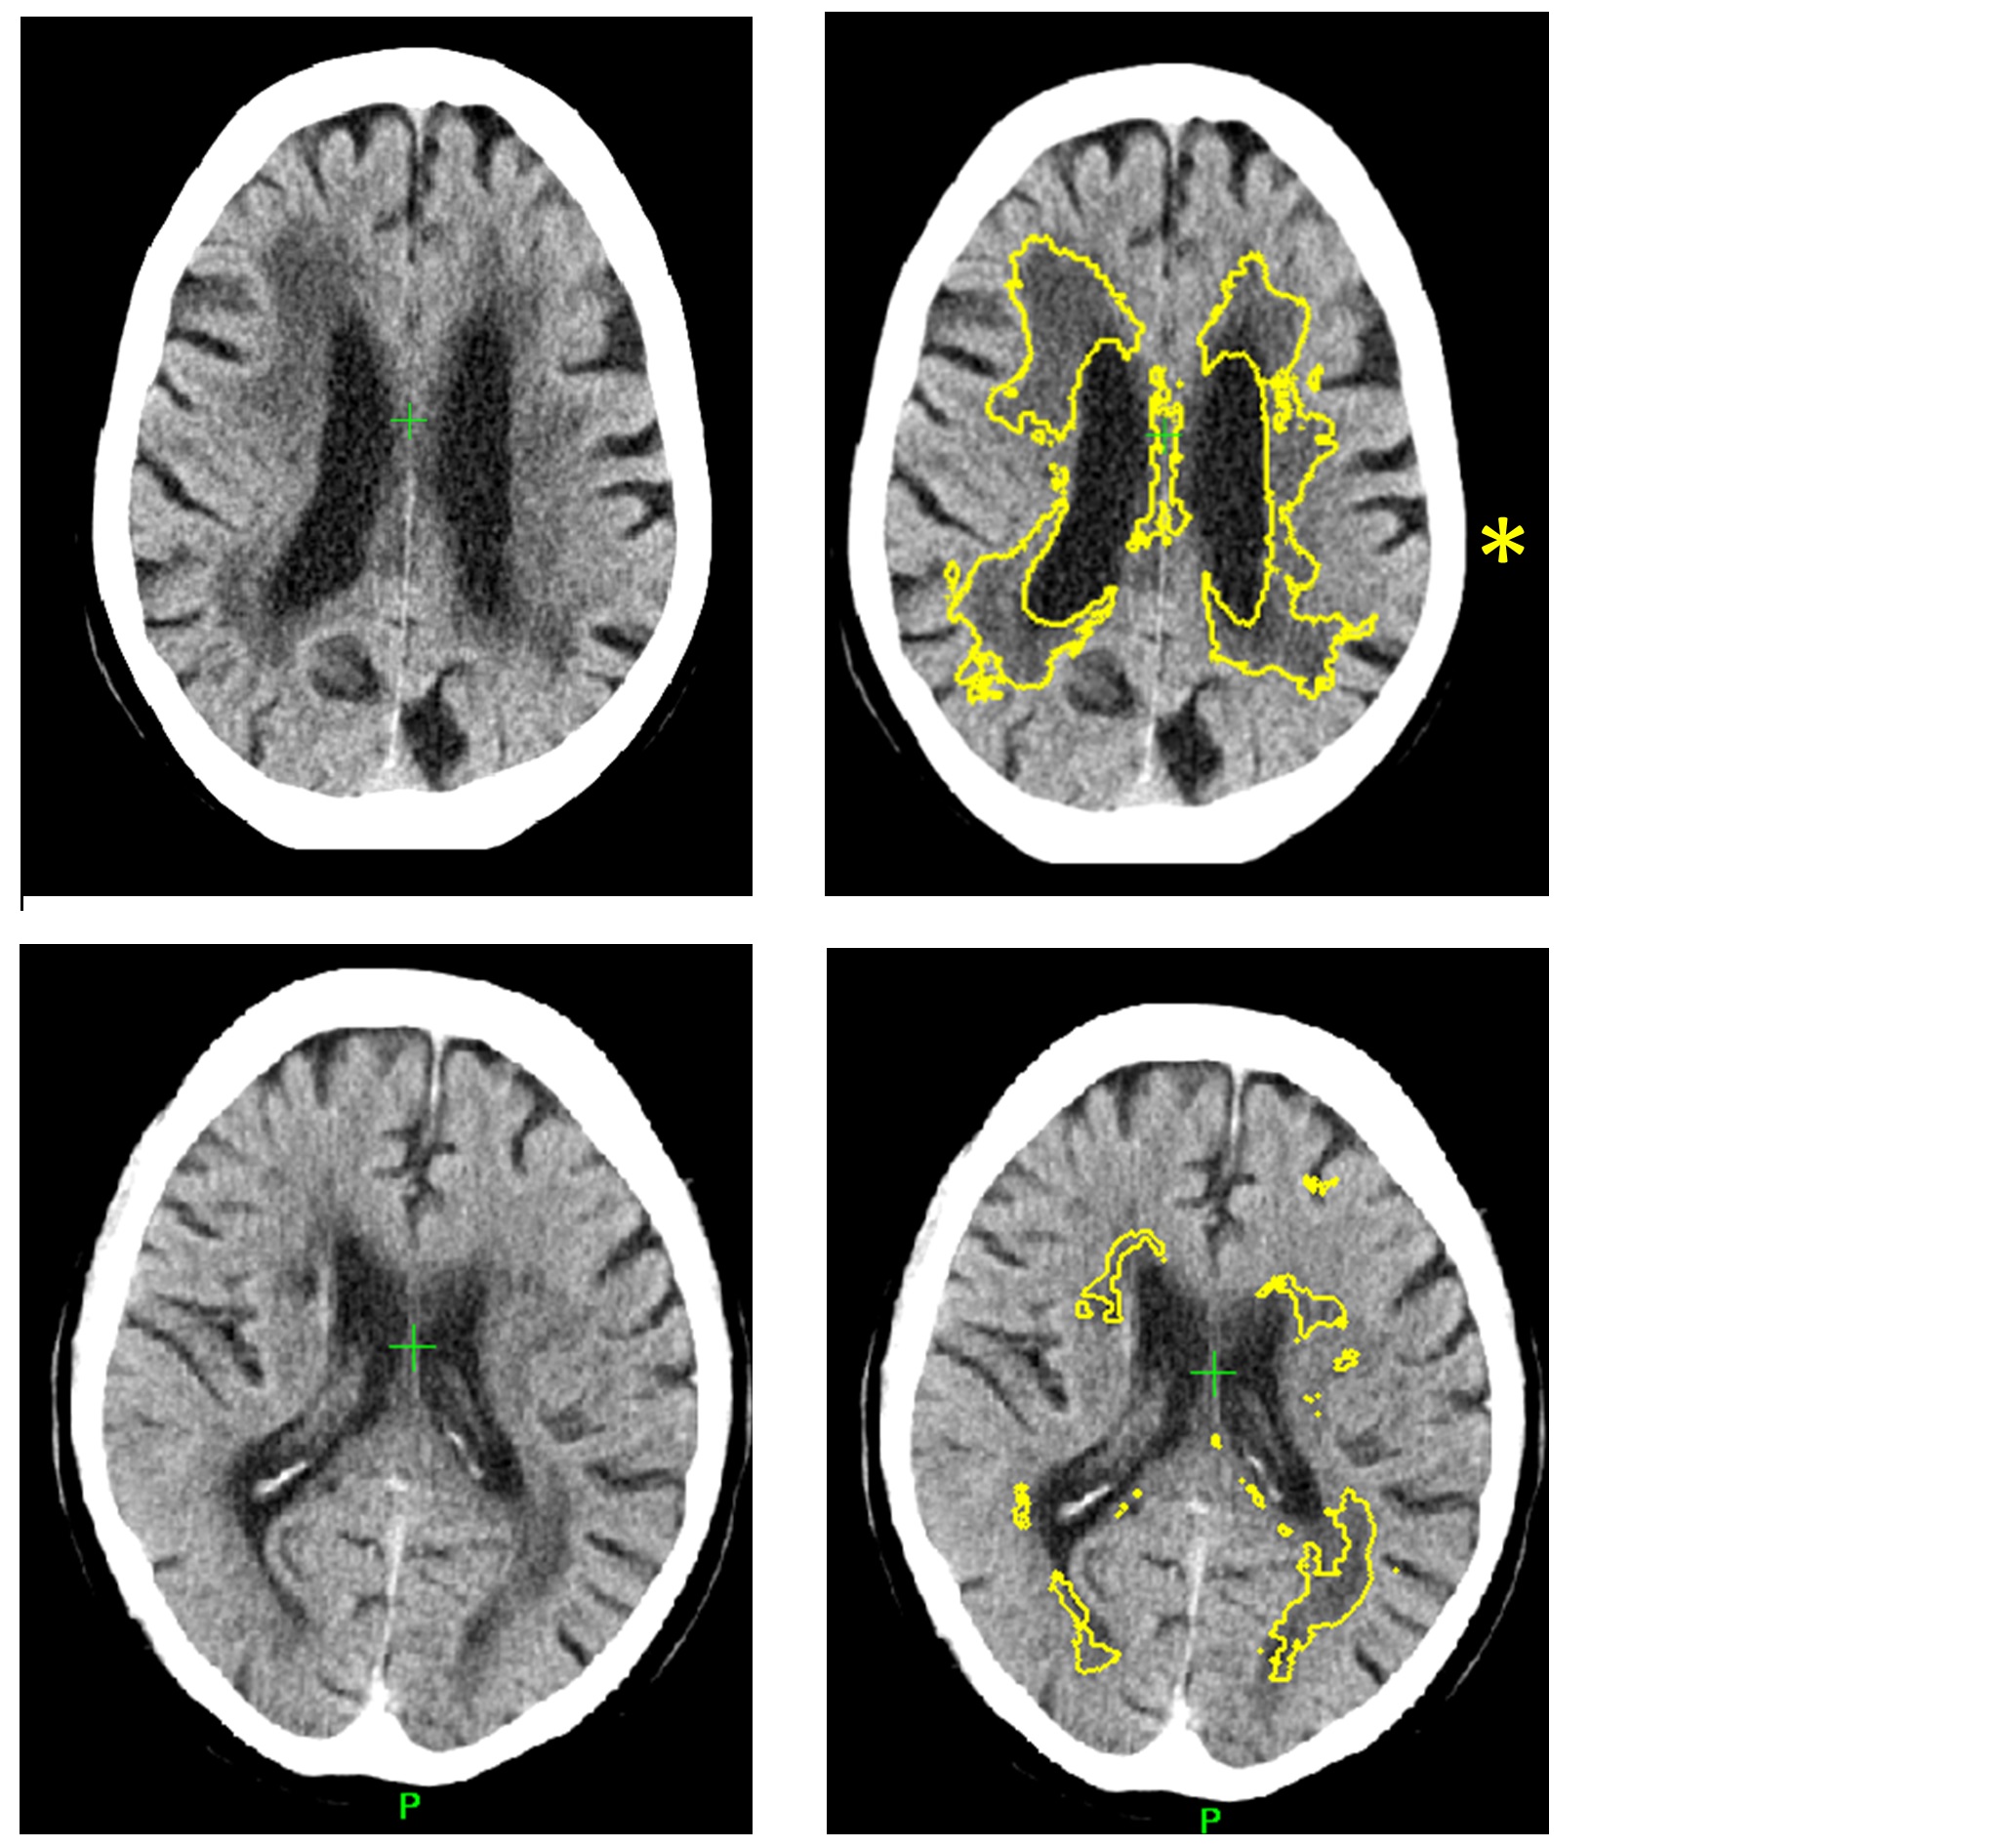

a An example brain CT of multi-infarct dementia. The brain CT showed …

Ct Scan Alzheimer’s Vs Normal – DementiaTalkClub.com

Dementia brain ct hi-res stock photography and images – Alamy

Dementia brain ct hi-res stock photography and images – Alamy